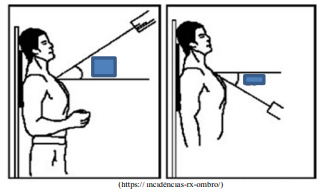

- Equipamentos RadiológicosOperação de Equipamentos e Posição Radiológica

O exame fornece uma visualização panorâmica do

sistema coletor. Comumente são utilizadas incidências

oblíquas do abdome para melhor demonstrar os trajetos

ureterais, e uma radiografia pós-miccional que

demonstra se o esvaziamento vesical é adequado.

- Equipamentos RadiológicosOperação de Equipamentos e Posição Radiológica

Os exames por imagens (radiografias) produzidos

pelos Técnicos e Tecnólogos em Radiologia são

importantíssimos para que o médico consiga um

diagnóstico eficaz e ajude o paciente a tratar a doença

da melhor maneira possível. Essas radiografias podem

ser adquiridas em incidências radiológicas diferentes,

possibilitando ao profissional visualizar diversas

estruturas nos diversos ângulos diferentes, tirando por

exemplo, estruturas de sobreposições ósseas, diminuir e

até aumentar magnificações das estruturas de interesse.

Observe a imagem e escolha a opção verdadeira sobre a

incidência.

(https:// incidências-rx-ombro/)

(https:// incidências-rx-ombro/)